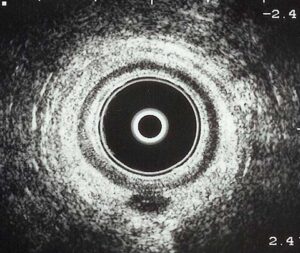

Ultrasonido endoanal.

Es el método más útil para identificar el origen interno de una fístula anorrectal, si tiene uno o varios trayectos, la relación de los trayectos con el músculo esfínter anal y si hay abscesos.